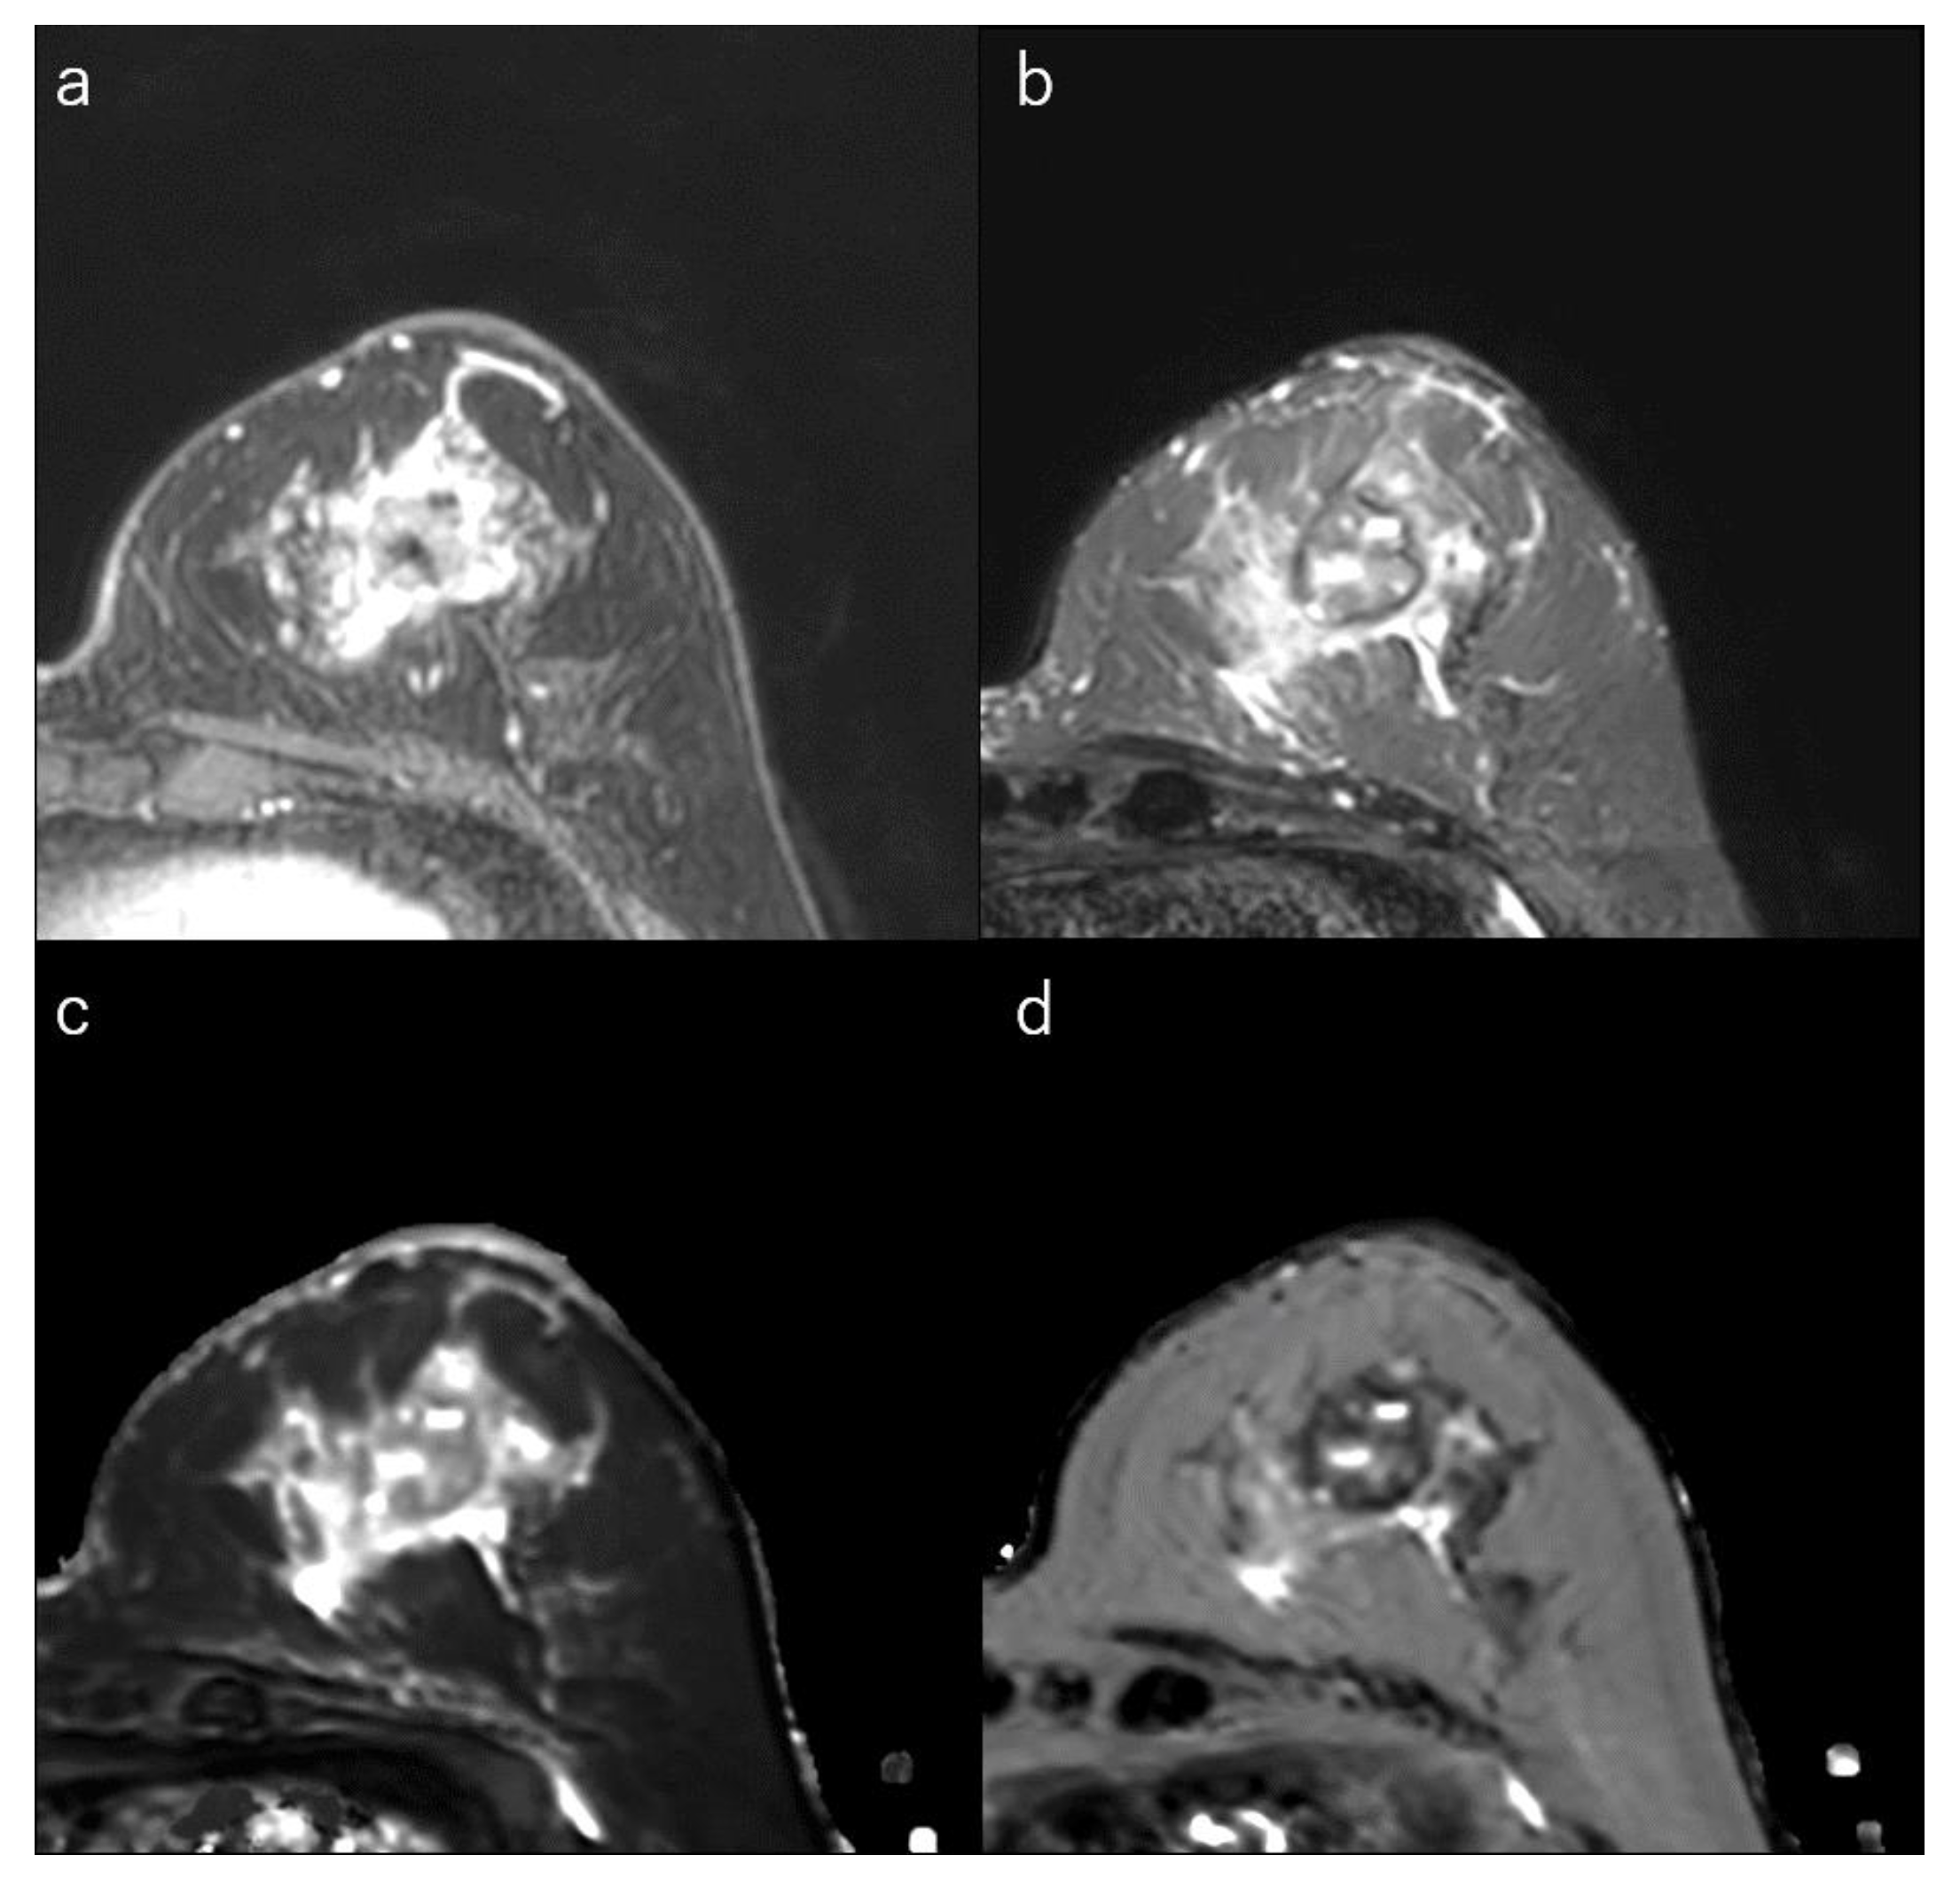

Figure 4.

(a) Dynamic contrast-enhanced MR image in a 32-year-old woman with luminal-B type breast cancer shows a heterogeneously enhanced oval mass with rim enhancement. (b) Short-tau inversion recovery image shows an intermediate signal mass. (c) T1 map (window width/centre = 1400/2400 ms) shows an intermediate signal mass; Mean T1 of the mass is 1174 ms on T1 map. (d) T2 map (window width/centre = 160/240 ms) shows an intermediate signal mass; mean T2 of the mass is 97 ms on T2 map.

Tumour roundness is positively correlated with Ki-67 index [154]. Luminal-B subtypes are more often associated with multicentric/multifocal disease than are luminal-A cancers [32,156,157] and are also enriched for fibroblast growth factor receptor gene amplification, which has been implicated in angiogenesis [33,158]. This may lead to a higher ratio of lesion enhancement on DCE-MRI and heterogeneous internal enhancement [32,33,41,159] (Figure 4).